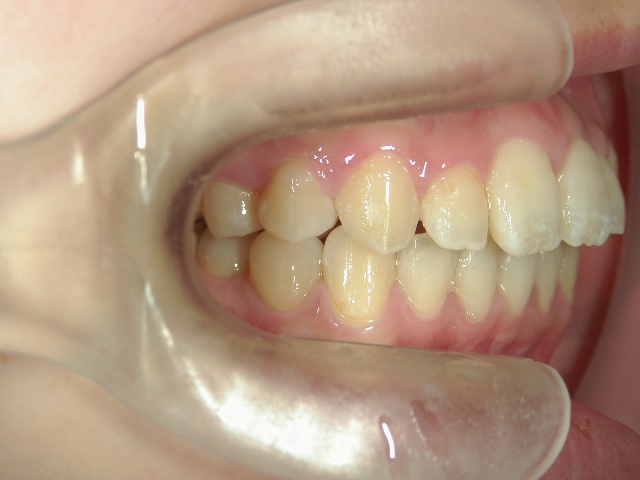

no.8_8495_治療前_左.jpgno.8_8495_治療前_正面.jpgno.8_8495_治療前_右.jpg

矯正歯科 治療前